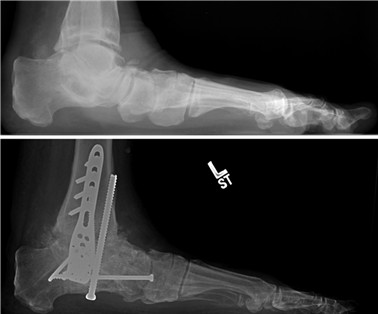

Clinical & Radiographic Imaging Archive

Clinical Image